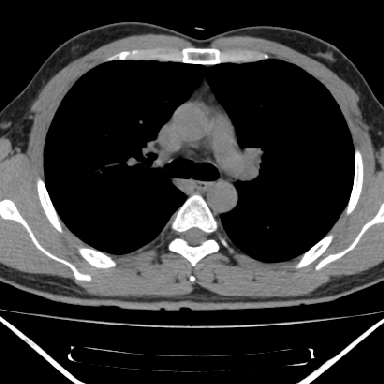

右上后纵隔脊柱旁类圆形肿块,边界光整,与胸腔呈钝角,首先考虑来源于肺外,神经源性肿瘤(神经鞘瘤可能大,神经鞘瘤)

病灶与椎间孔间存在脂间隙,病灶较大,椎间无明显异常改变,与胸膜移行处可见尾状影,考虑胸膜肿瘤,以良性间皮瘤可能性大

病灶最大径线处于肋间隙,不排除起源于肋神经源性肿瘤

右上后纵隔脊柱旁类圆形肿块,边界光整,与胸腔呈钝角,首先考虑来源于纵膈,神经源性肿瘤可能大。

右上后纵隔脊柱旁见长椭圆形肿块,边界光整,与胸壁呈钝角。周围骨质未见异常。

考虑、1、后纵隔神经源性肿瘤;

2、不除外单发胸膜间皮瘤。

右上后纵隔脊柱旁类圆形肿块,边界光整,与胸膜呈钝角,首先考虑来源于肺外,神经源性肿瘤(神经纤维瘤可能大)。